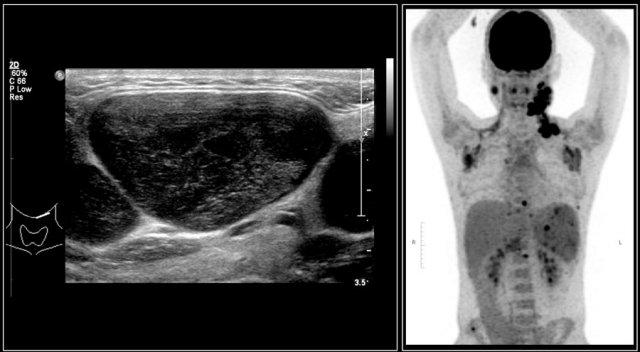

Hình ảnh của một bé trai mười bốn tuổi với khối sưng không đau ở cổ bên trái.

Siêu âm cho thấy nhiều hạch bạch huyết giảm âm phóng to, không có rốn hạch tăng âm.

Đây là một bé trai mười bốn tuổi khác với tình trạng sưng không đau ở cổ bên trái.

Siêu âm cho thấy nhiều hạch bạch huyết to.

Continue with the MR and PET/CT…

Hình ảnh STIR mặt phẳng coronal cho thấy các khối hạch bạch huyết bệnh lý tương tự như trên PET-CT.

The diagnosis was Hodgkin’s lymphoma.